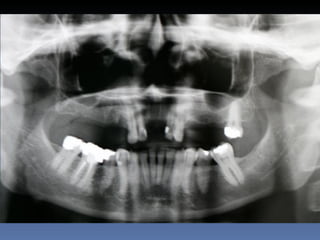

BOX 2

Sebastião Moreira Souza

Idade – 49 anos

Sexo – Masculino

Raça – Caucasiana

ASA – II

Data- 23-04-2012

Diagnóstico: Desdentado total maxila

Plano de tratamento:          Reabilitação com 6 blocos

“onlay” e “sinus-llift” bilateral, provenientes de Úmero

fresco-congelado (FFB); reabertura para instalação

de 6 implantes dentários endo-ósseos e reabilitação

protética fixa.

21-09-2011

23-04-2012

Zona 2.3

3,5 mm

Pré reabilitação

Reabilitação Aloenxerto

Instalação Implantes